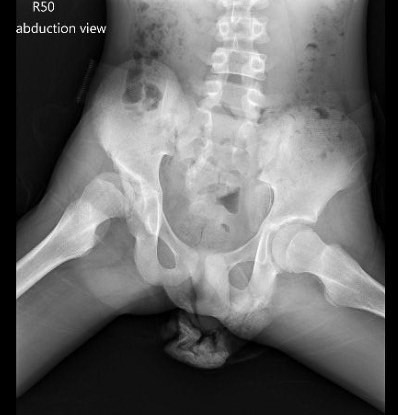

經過X 光與電腦斷層檢查,黃盟仁醫師發現十五歲的小辰不僅有長短腳的情形,他的右側髖關節也出現半脫位的症狀。

髖關節位於骨盆與大腿骨之間,由骨盆上的髖臼與大腿骨上方圓球形的股骨頭組合而成,是人體最大的關節,也是人類站立、步行最重要的關節。兩者結合的周圍有關節囊、韌帶和肌肉包圍,髖關節脫位就是股骨頭脫離了髖骨的凹臼,骨骼之間相互摩擦後,髖關節功能會損壞,將影響正常站立與行走。雖然小辰目前並沒有出現疼痛的情形,但為了避免日後髖關節嚴重磨損,出現退化性關節炎,黃盟仁醫師建議進行「髖關節三位截骨矯正手術」。但此刻卻面臨極大的挑戰——小辰的迴避與爸爸的擔憂。

X 光檢查發現小辰右側股骨頭脫離了髖骨的凹臼,形成髖關節半脫位。圖/黃盟仁醫師提供